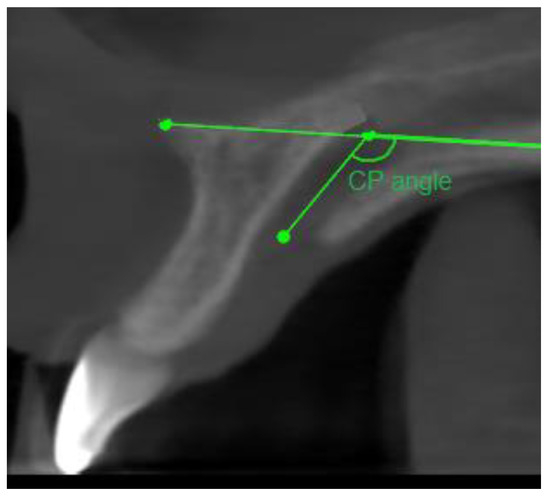

- Sagittal plane:

- Angle formed by the long axis of the incisor and the palatine plane—CP angle.

- Angle formed by the long axis of the incisive canal and the palatine plane—IP angle.